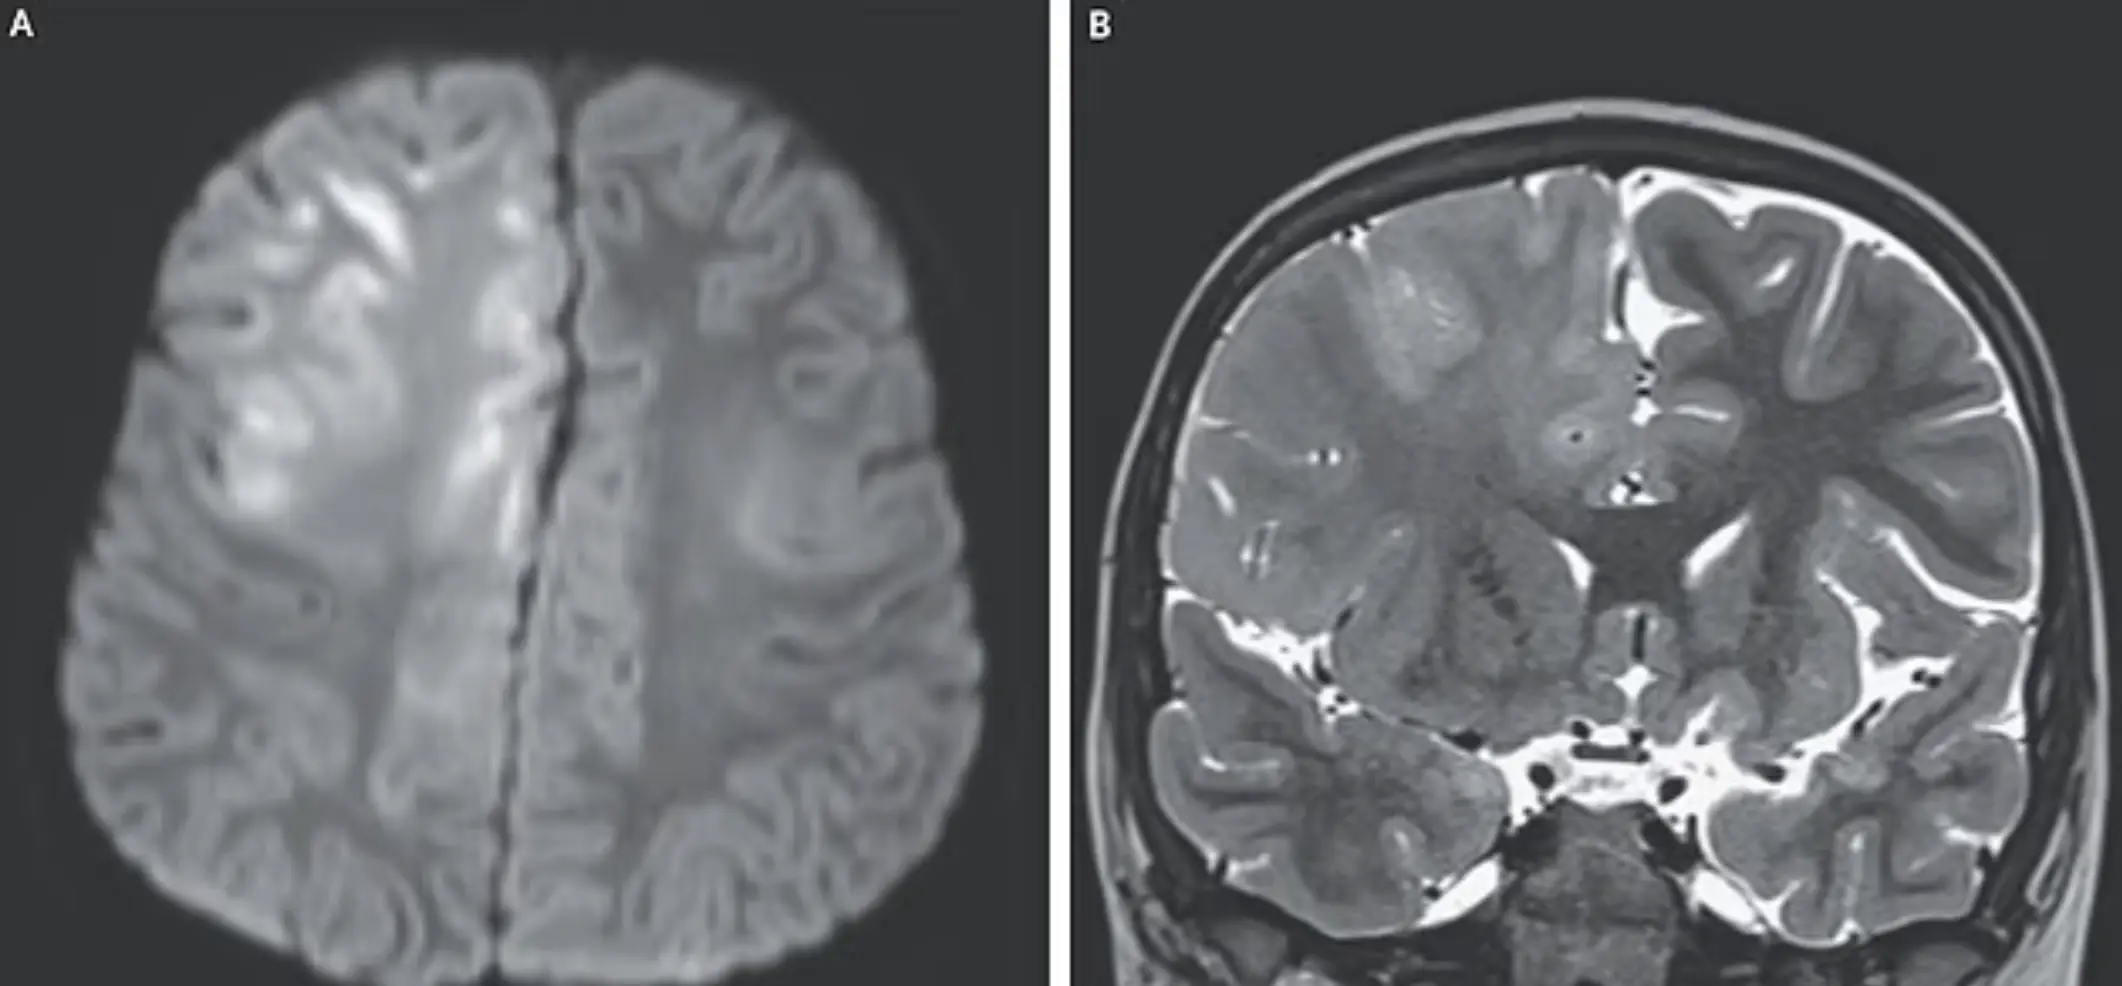

The young child had contracted measles when he was just seven months old and his family thought he had made a full recovery. However, the minor began experiencing cognitive deterioration and seizures when he reached the age of six, with doctors diagnosing him with subacute sclerosing panencephalitis (SSPE).

While measles will often present symptoms such as a common cold, a rash and high fever at the start, the virus can persist in the body for a number of years after initial exposure.

Certain mutations of the disease can lead to SSPE years later.

Encephalitis International explains how SSPE typically starts between six and eight years after a measles infection, and is 'related to destruction of the infected brain cells'.